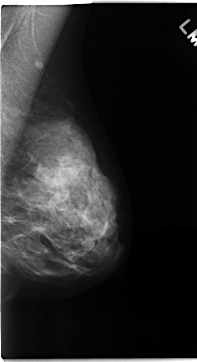

C_0167_1.LEFT_MLO

LEFT_MLO LINES 4704 PIXELS_PER_LINE 2552 BITS_PER_PIXEL 12 RESOLUTION 50 NON_OVERLAY